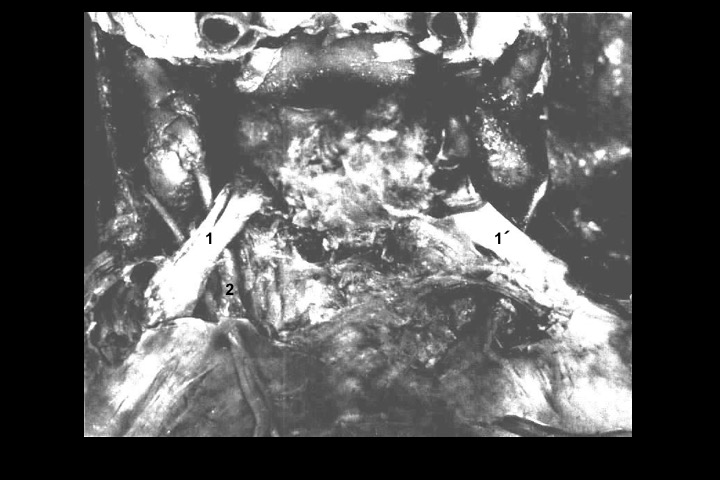

O Prof. Emérito da UFRJ Dr. Adalmir Morterá Dantas está disponibilizando através de nosso website e de nosso canal youtube (cursobom) o Museu de Neuroanatomia, no intuito de promover esta área de conhecimento junto aos estudantes de Medicina.

As figuras são apresentadas em 4 vídeos no youtube e podem ser obtidas via download clicando-se na figura em questão.